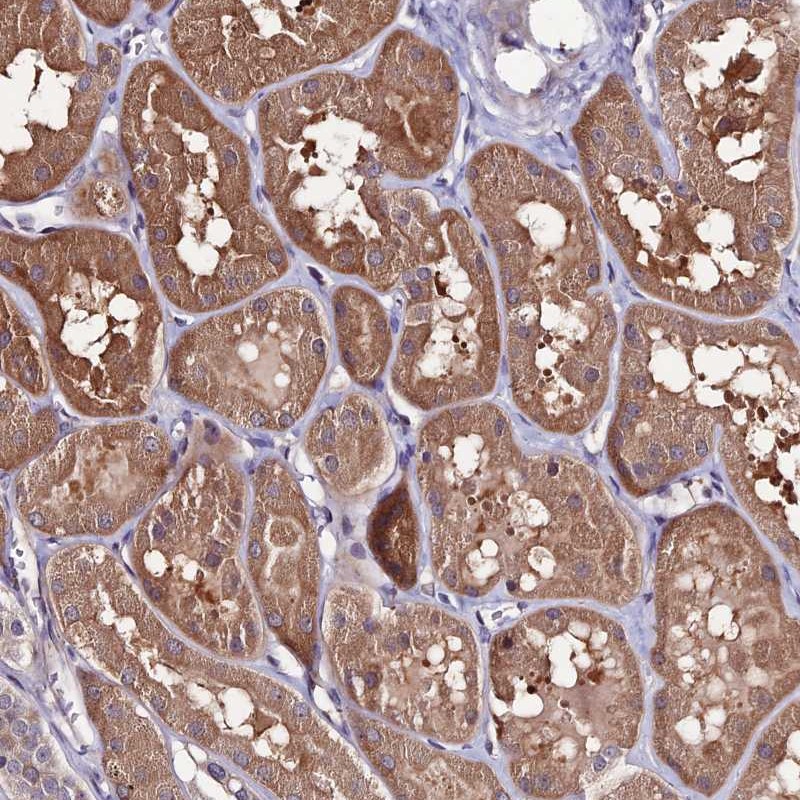

Immunohistochemical staining of human kidney shows moderate cytoplasmic positivity in tubular cells.